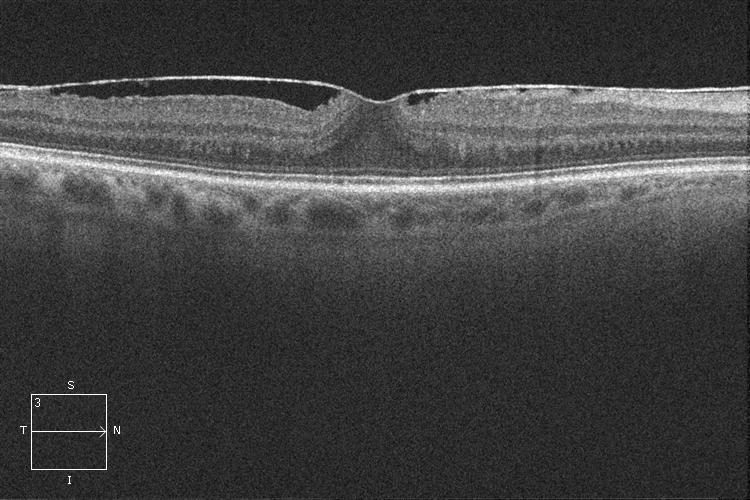

OCT. Membrana epirretiniana

OCT. Membrana epirretiniana antes de la cirugía